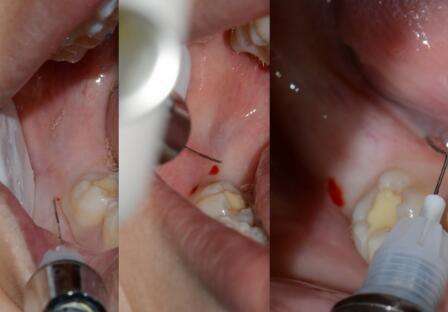

3、软组织损伤

牙龈组织撕裂伤是最为常见的拔牙术的术中并发症,牙龈损伤,多为撕裂伤,也是术后出血主要的原因之一;

所以做拔牙手术时,一旦上颌牙拔出时用力不当,就有可能导致这种并发症的产生。